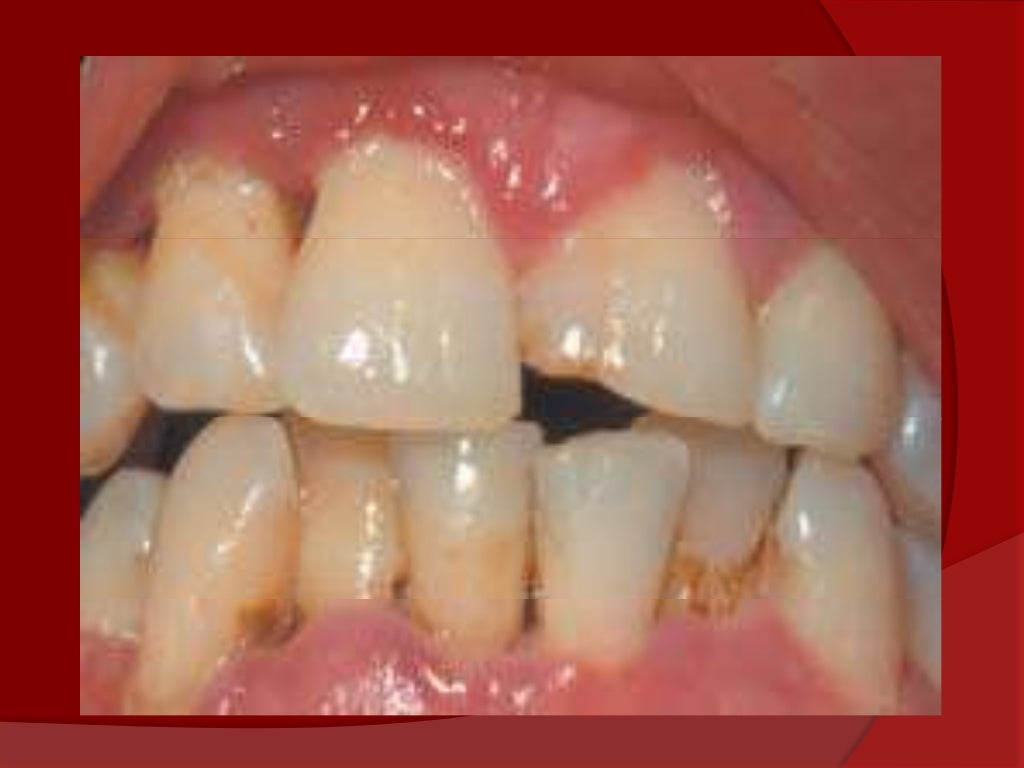

Gingivitis Necrotizante . Symptoms are acute pain, bleeding, and foul breath. Los síntomas son dolor agudo, sangrado y aliento de olor. Diagnosis is based on clinical findings. Treatment is gentle debridement, improved oral hygiene, mouth rinses, supportive care, and, if debridement must be delayed, antibiotics. La gingivitis ulcerativa necrosante aguda es una infección dolorosa de las encías. Acute necrotizing ulcerative gingivitis (anug) is a rare infectious disease of the gum tissue, affecting <1% of the population. Covers the management of acute necrotizing ulcerative gingivitis where the gums are acutely painful and swollen; The aim of this narrative literature review was to describe the available evidence on the diagnosis and treatment of ng, and present. Anug presents as an acute, painful, and destructive. They bleed easily and have. There are three major forms: It has an acute clinical presentation with the distinctive. Acute necrotizing ulcerative gingivitis is a painful infection of the gums. Necrotizing ulcerative gingivitis (nug) is a typical form of periodontal diseases.

Gingivitis Necrotizante La gingivitis ulcerativa necrosante aguda es una infección dolorosa de las encías. It has an acute clinical presentation with the distinctive. Diagnosis is based on clinical findings. They bleed easily and have. La gingivitis ulcerativa necrosante aguda es una infección dolorosa de las encías. Acute necrotizing ulcerative gingivitis is a painful infection of the gums. There are three major forms: The aim of this narrative literature review was to describe the available evidence on the diagnosis and treatment of ng, and present. Treatment is gentle debridement, improved oral hygiene, mouth rinses, supportive care, and, if debridement must be delayed, antibiotics. Anug presents as an acute, painful, and destructive. Symptoms are acute pain, bleeding, and foul breath. Covers the management of acute necrotizing ulcerative gingivitis where the gums are acutely painful and swollen; Los síntomas son dolor agudo, sangrado y aliento de olor. Necrotizing ulcerative gingivitis (nug) is a typical form of periodontal diseases. Acute necrotizing ulcerative gingivitis (anug) is a rare infectious disease of the gum tissue, affecting <1% of the population.